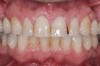

Fig 9. Preoperative view (Fig 9), preparation with composite block-out restoration (Fig 10), and final cementation of CL-IIb material (Fig 11) (final ceramic contour and stain by Steve Lee, CDT, MDC).

Figure 9

Fig 10. Preoperative view (Fig 9), preparation with composite block-out restoration (Fig 10), and final cementation of CL-IIb material (Fig 11) (final ceramic contour and stain by Steve Lee, CDT, MDC).

Figure 10

Fig 11. Preoperative view (Fig 9), preparation with composite block-out restoration (Fig 10), and final cementation of CL-IIb material (Fig 11) (final ceramic contour and stain by Steve Lee, CDT, MDC).

Figure 11